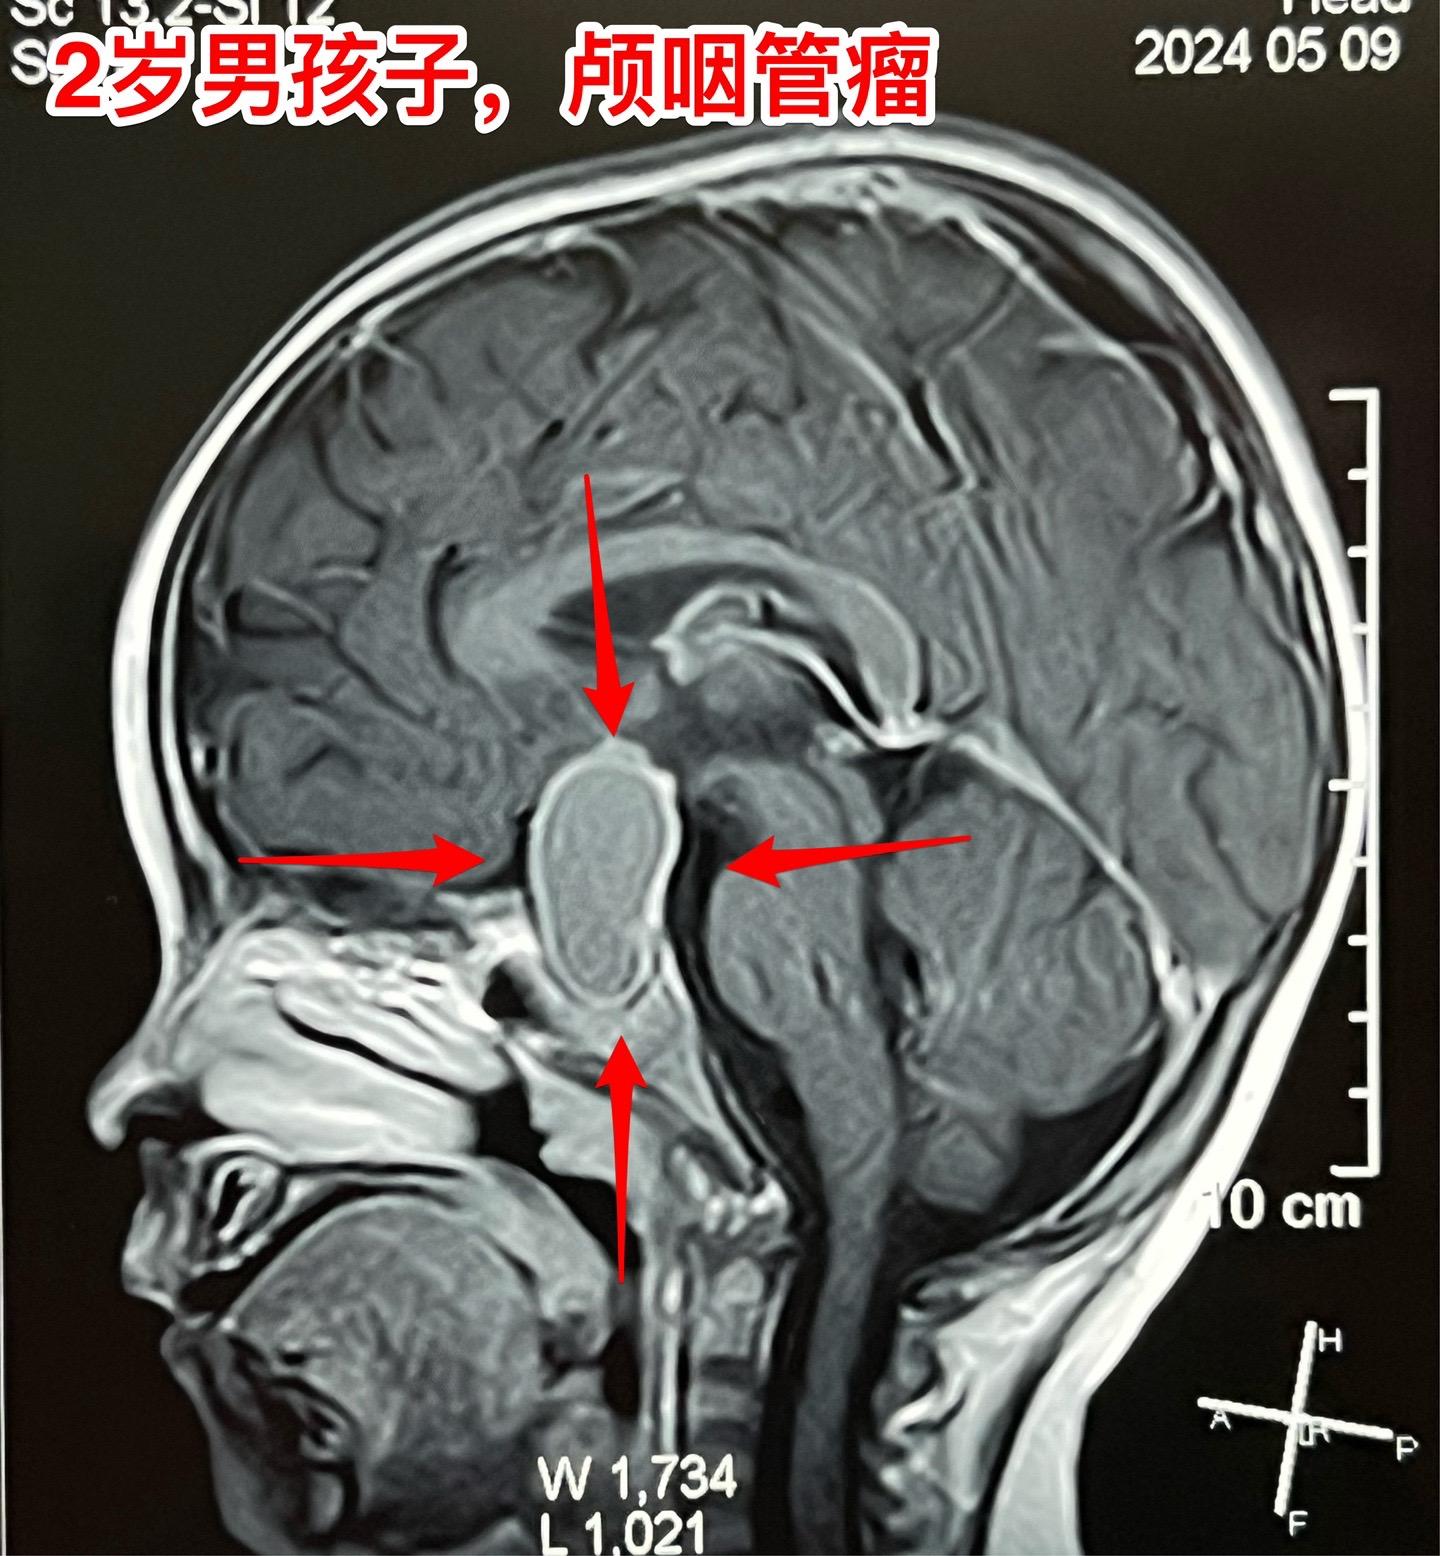

老天造孽哦,才2岁的孩子就患上颅咽管瘤。CT和磁共振显示是典型的颅咽管瘤,有钙化。视神经受压,视力有下降(还没有到失明的程度),不得不接受手术治疗。5月11日顺利将肿瘤完全切除。希望肿瘤不复发。